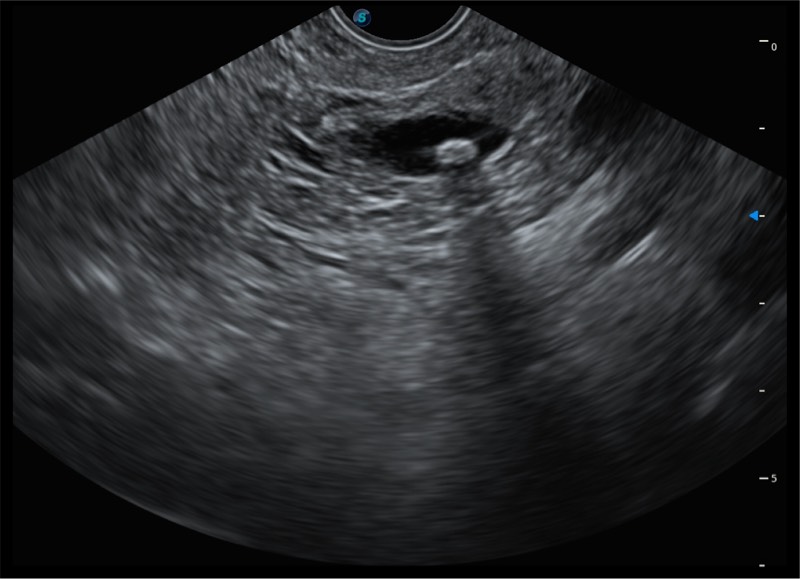

4.0mm大钳道

12.6mm先端部外径

150°超声扫描角度